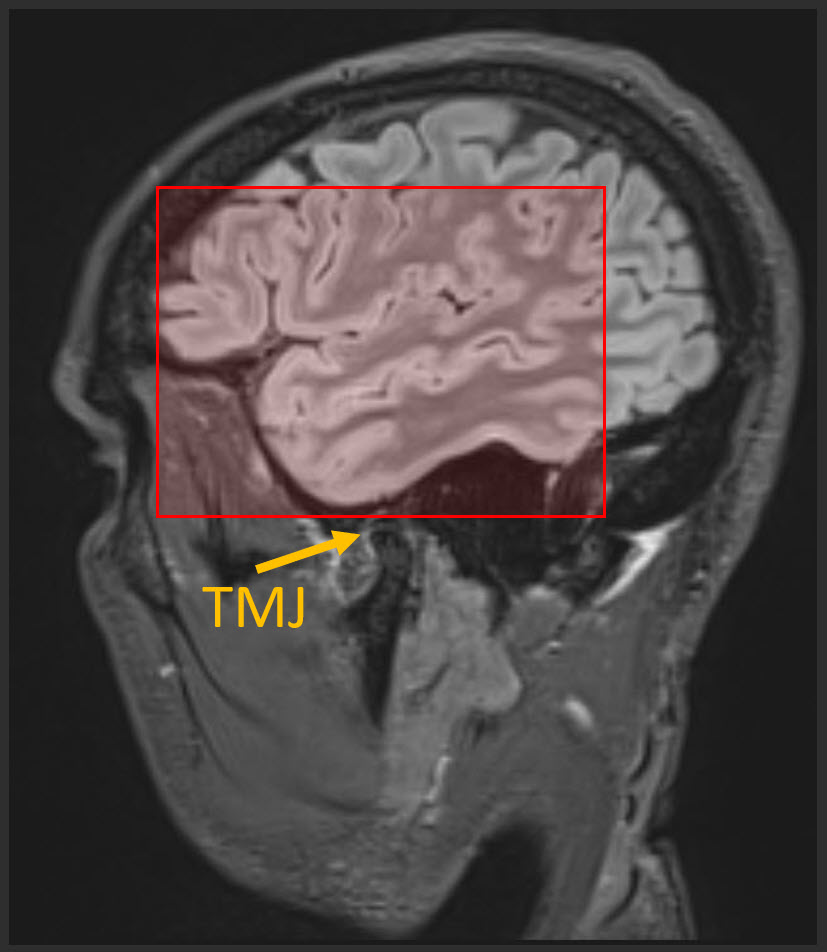

• Inferior-most slice in stack should be centered on the TMJ (see pic below).

Sagittal FLAIR image showing anatomic coverage this MMRI sequence.